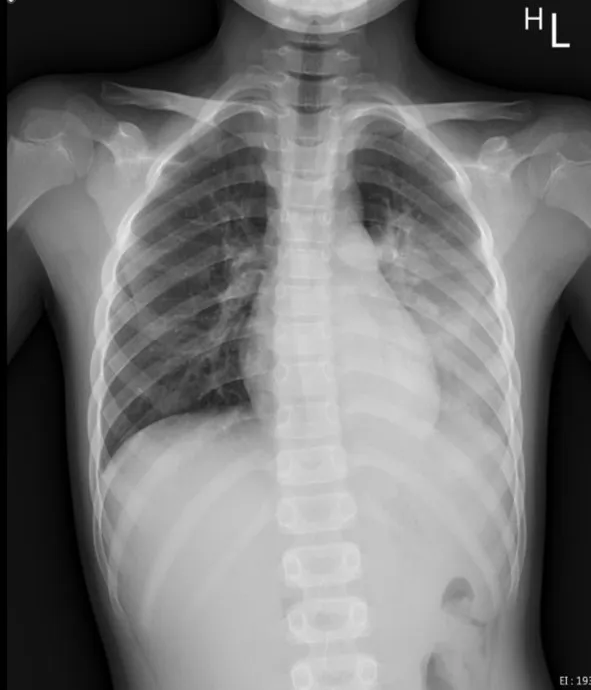

花蓮慈濟醫院曾收治一名8歲男童因呼吸道融合病毒(RSV)合併肺炎鏈球菌及鼻病毒的感染,造成左側大葉性肺炎,就醫檢查胸部X光發現左邊肺部幾乎白化住院治療。陳明群指出,在過去的兒科臨床案例中,這種RSV造成年紀較大的孩子發生肺炎的案例是相對少見的,大多都是4、5歲以下的小小孩免疫系統還未成熟且細支氣管較細小,被病毒攻擊時才會這麼嚴重。